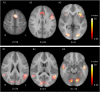

Materials and methods: fMRI data was acquired from 22 children with rolandic epilepsy and 22 age-matched controls (age range: 8-14 years), both at rest and using word-generation and reading tasks. Activation map analysis revealed no group differences (FWE-corrected, p < 0.05) and was therefore used to define regions of interest for pooled (patients and controls combined) language activation. Independent component analysis with dual regression was used to identify the sensorimotor resting-state network in all subjects. The associated functional connectivity maps were compared between groups at the regions of interest for language activation identified from the task data. In addition, neuropsychological language testing (Clinical Evaluation of Language Fundamentals, 4th edition) was performed.

Results: Functional connectivity with the sensorimotor network was reduced in patients compared to controls (p = 0.011) in the left inferior frontal gyrus, i.e. Broca's area as identified by the word-generation task. No aberrant functional connectivity values were found in the other regions of interest, nor were any associations found between functional connectivity and language performance. Neuropsychological testing confirmed language impairment in patients relative to controls (reductions in core language score, p = 0.03; language content index, p = 0.01; receptive language index, p = 0.005).

Conclusion: Reduced functional connectivity was demonstrated between the sensorimotor network and the left inferior frontal gyrus (Broca's area) in children with RE, which might link epileptiform activity/seizures originating from the sensorimotor cortex to language impairment, and is in line with the identified neuropsychological profile of anterior language dysfunction.